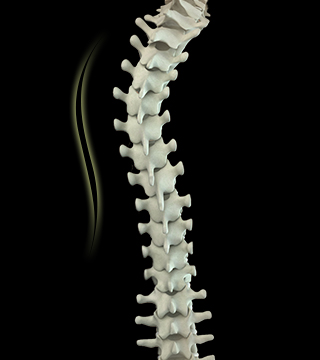

• 척추측만증

앞이나 옆에서 전체 척추의 배열을 보았을 때 척추의 곡선이 과도하게 휘어진 증상을 척추측만증이라 합니다.

척추측만증 치료방법

• 비수술적 치료 보조기 착용, 운동치료

• 수술적 치료 성장이 멈춘 후 측만 정도가 50도 이상일 경우 또는 신경장애·호흡장애 등 합병증 동반시 수술적 치료가 필요합니다.

척추측만증 교정술